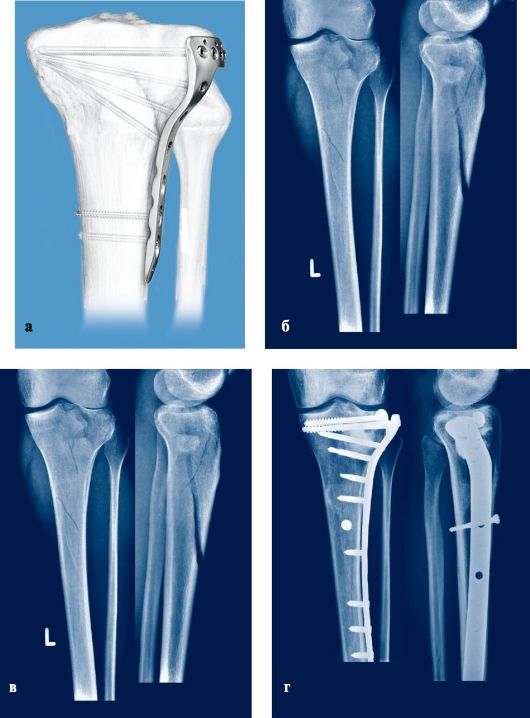

В отделении проводятся все виды оперативных вмешательств при переломах конечностей:

•  апаратами внешней фиксации;

• лечение с помощью имплантов с угловой стабильностью (LCP-DCP);

• интрамедулярный блокируемый остеосинтез;

Все оперативные вмешательства проводятся по современным методикам под контролем интраоперационного рентгенконтоля (ЭОП), с применением философии биологического остеосинтеза и принципов малотравматичности и малоинвазивности.